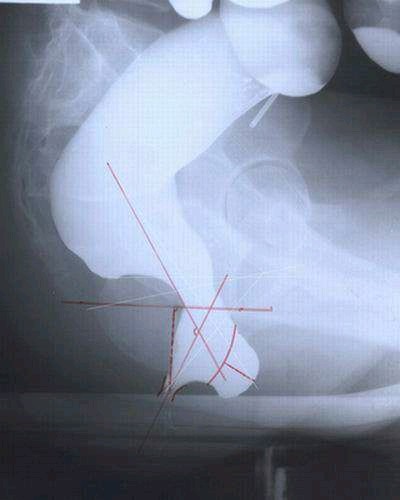

方法:口服含有不透X线标记物的胶囊,通过X光观察标记物的排出情况。

作用:主要用于鉴别慢传输型便秘,即肠道蠕动功能减慢的情况,判断肠道蠕动是否减慢,确定是否为慢传输型便秘。如果标记物在胃结肠段滞留时间延长(通常超过5天),提示慢传输性便秘。

具体方法有:

患者口服含不透射线标记物的胶囊,通常在服用后第3天或第5天拍摄腹部X线片,通过观察标记物在肠道中的分布来评估肠道蠕动情况。

方法:在直肠内注入造影剂,模拟排便过程并拍摄X线或MRI图像。

主要作用:用于诊断出口梗阻型便秘,能发现直肠前突、直肠黏膜脱垂、肛门失弛缓、直肠内套叠、盆底肌肉功能障碍等。

患者通过直肠灌注造影剂,然后在排便时进行X线成像或MRI检查,记录排便过程中的直肠、肛管及盆底的动态变化。